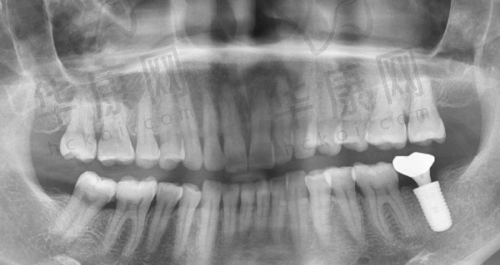

重庆中三口腔全口仕诺康种植牙的实例展示

重庆中三口腔有许多成功的全口仕诺康种植牙实例。例如,一位老年患者因全口牙齿缺失,生活受到较大影响,饮食只能选择软烂食物,营养摄入不足。在重庆中三口腔接受全口仕诺康种植牙手术后,修复了正常的咀嚼功能,能够像正常人一样享受美食,生活质量得到了极大提高。

这些实例不仅体现了重庆中三口腔在全口仕诺康种植牙项目上的技术实力,也证明了该项目能够为患者带来实实在在的好处。